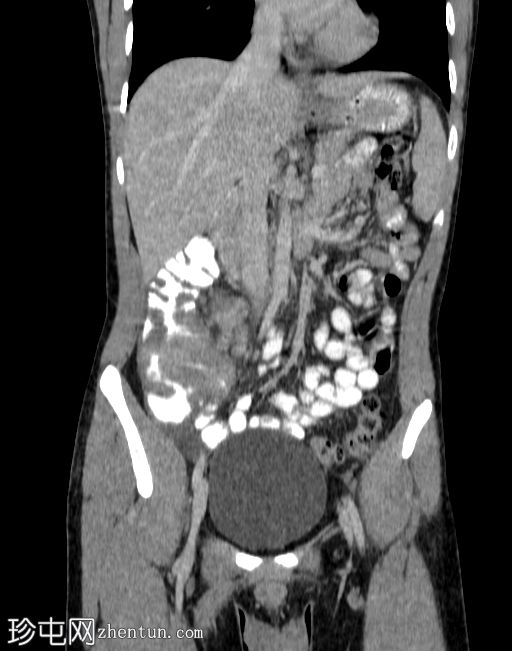

轴位增强扫描(门静脉期)

可见盲肠和末端回肠弥漫性环周肠壁增厚,导致严重的肠腔狭窄。可见多个区域淋巴结肿大,最大者大小为2.4 x 2.2 cm,伴中央坏死。

右侧结肠旁沟可见少量游离液体和脂肪条索影,盆腔内可见少量游离液体。